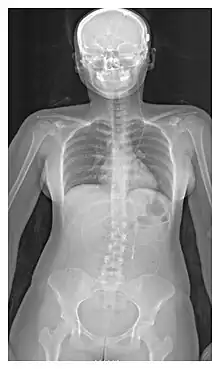

L'emplacement de la dérivation est déterminé par le neurochirurgien en fonction du type et de l'emplacement du blocage provoquant l'hydrocéphalie. Tous les ventricules cérébraux sont candidats à la dérivation. Le cathéter est le plus souvent placé dans l'abdomen, mais d'autres emplacements incluent le cœur et les poumons. les dérivations peuvent souvent porter le nom de la voie utilisée par le neurochirurgien. L'extrémité distale du cathéter peut être située dans à peu près n'importe quel tissu comportant suffisamment de cellules épithéliales pour absorber le LCR entrant. Ci-dessous quelques plans de routage courants pour les dérivations cérébrales :

| Dérivation ventriculo-péritonéal (Dérivation VP) | Cavité péritonéale |

| Dérivation ventriculo-pleural (Dérivation VPL) | Cavité pleurale |